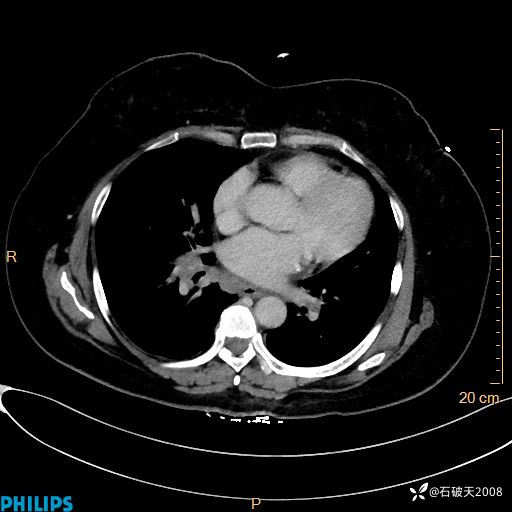

纵隔窗